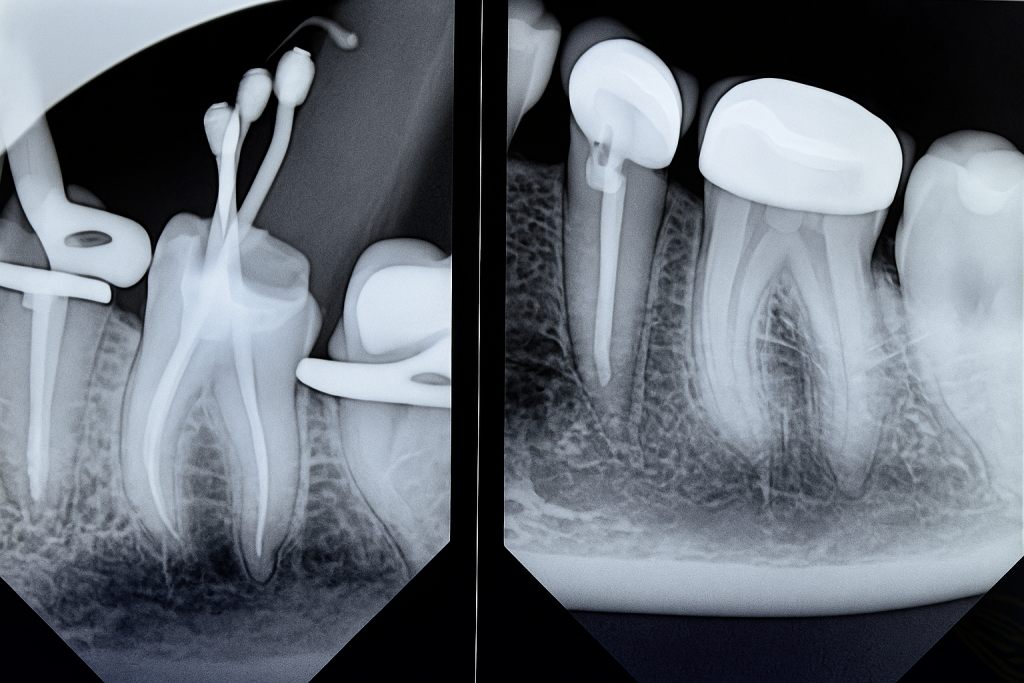

Obturation performed with Bioceramic Sealer (Endo Sequence BC) and warm vertical condensation to ensure apical seal and coronal adaptation (Fig 3).

Radiograph confirmed ideal obturation, core adaptation, and marginal integrity (Fig 3). The final restoration blended esthetically and functionally with the dentition (Fig 5).

- Fig 3: Post-obturation radiograph confirming dense 3-D fill.